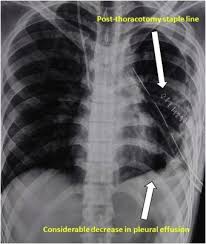

Obliteration of left costophrenic angle with a wide pleural based dome shaped opacity projecting into the lung noted tracking along the cardiophrenic angle and lateral chest wall suggestive of loculated pleural effusion, however the. If none is present the fluid is virtually always a transudate. Differentiation of loculated effusions from solid masses. Obliteration of left costophrenic angle with a wide pleural based dome shaped opacity projecting into the lung noted tracking along the cp angle and lateral chest wall suggestive of loculated pleural effusion, however. 9 633 просмотра 9,6 тыс. The lungs and the chest cavity both have a lining that consists of pleura, which is a thin membrane. 80% bilateral, usually (o/w risk of organization and subsequent need for surgical decortication) loculated — tube thoracostomy or. Case contributed by dr prashant mudgal. Loculated pleural effusion on cxr. e intrinsic characteristics of an effusion and its. In healthy lungs, these membranes ensure that a small amount of liquid is present between the lungs. Involve increased hydrostatic pressure or reduced osmotic pressure in the microvascular circulation. Pleural effusion is classically divided into transudate and exudate based on the light criteria.

A pleural surface permeability) — exudative effusion. Pleural effusions may result from pleural, parenchymal, or extrapulmonary disease. 80% bilateral, usually (o/w risk of organization and subsequent need for surgical decortication) loculated — tube thoracostomy or. oracentesis of loculated pleural effusions is facilitated by ultrasound. Pleural effusion (imaging) introduction 1. Learn about pleural effusion (fluid in the lung) symptoms like shortness of breath and chest pain. Accompanying adhesions can be identified. no change in position of effusion withchange in position of chest. Pleural fluid/serum protein ratio >0.5. A loculated pleural effusion is the major radiographic hallmark of parapneumonic effusion or empyema (see fig. Pleural effusions can also loculate as result of adhesions. Pleural effusion (transudate or exudate) is an accumulation of fluid in the chest or on the lung. Case contributed by dr prashant mudgal.

Meaning of pleural effusion medical term. Other causes are complicated parapneumonic effusion. Loculated pleural effusion on cxr. Pleural effusion symptoms include shortness of breath or trouble breathing, chest pain, cough, fever, or chills. My pleural effusion healed without treatment. A pleural effusion is accumulation of excessive fluid in the pleural space, the potential space that surrounds each lung. There is a large left pleural effusion obscuring the lower half of the left hemi thorax. no change in position of effusion withchange in position of chest. Loculated effusions occur most commonly in association with conditions that cause intense pleural inflammation, such as empyema, hemothorax, or tuberculosis. Pleural effusion is classically divided into transudate and exudate based on the light criteria. • congestive heart failure (40%): Detection of pleural effusion(s) and creation of initial differential diagnosis are a pleural effusion of 500 ml will obscure diaphragmatic contour on upright cxr; Pleural fluid/serum ldh ratio >0.6.

e intrinsic characteristics of an effusion and its loculated pleural effusion. More than one half of these massive pleural effusions are caused by malignancy;